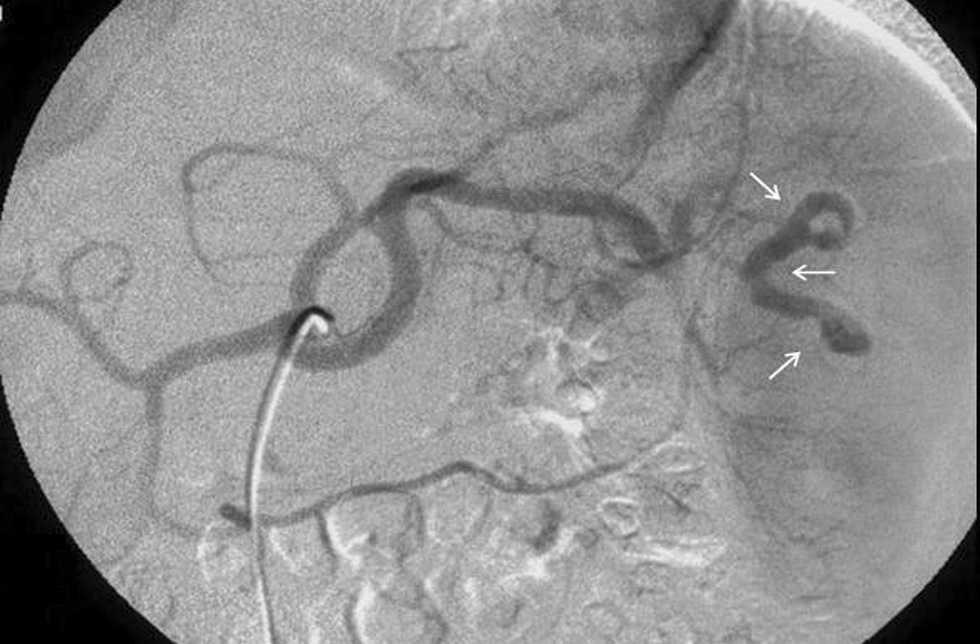

Paciente varón de 16 años que, tras experimentar un accidente de moto, fue atendido por un dolor abdominal. La analítica demostró una disminución del hematocrito en un 35%. La tomografía computarizada (TC) en la primera hora del ingreso mostró una laceración esplénica y hemoperitoneo en cantidad moderada. La TC de control realizada a los 3 días reveló la presencia de contraste extravascular contenido en la lesión esplénica (cabezas de flecha en fig. 1), por lo que se estableció el diagnóstico de seudoaneurisma intraesplénico. En arteriografía se confirmó la presencia de un trayecto de depósito de contraste extravascular dependiente de una rama intraesplénica de la arteria esplénica (flechas en fig. 2), que fue selectivamente embolizada con éxito. El paciente evolucionó de manera adecuada y fue dado de alta sin complicaciones.